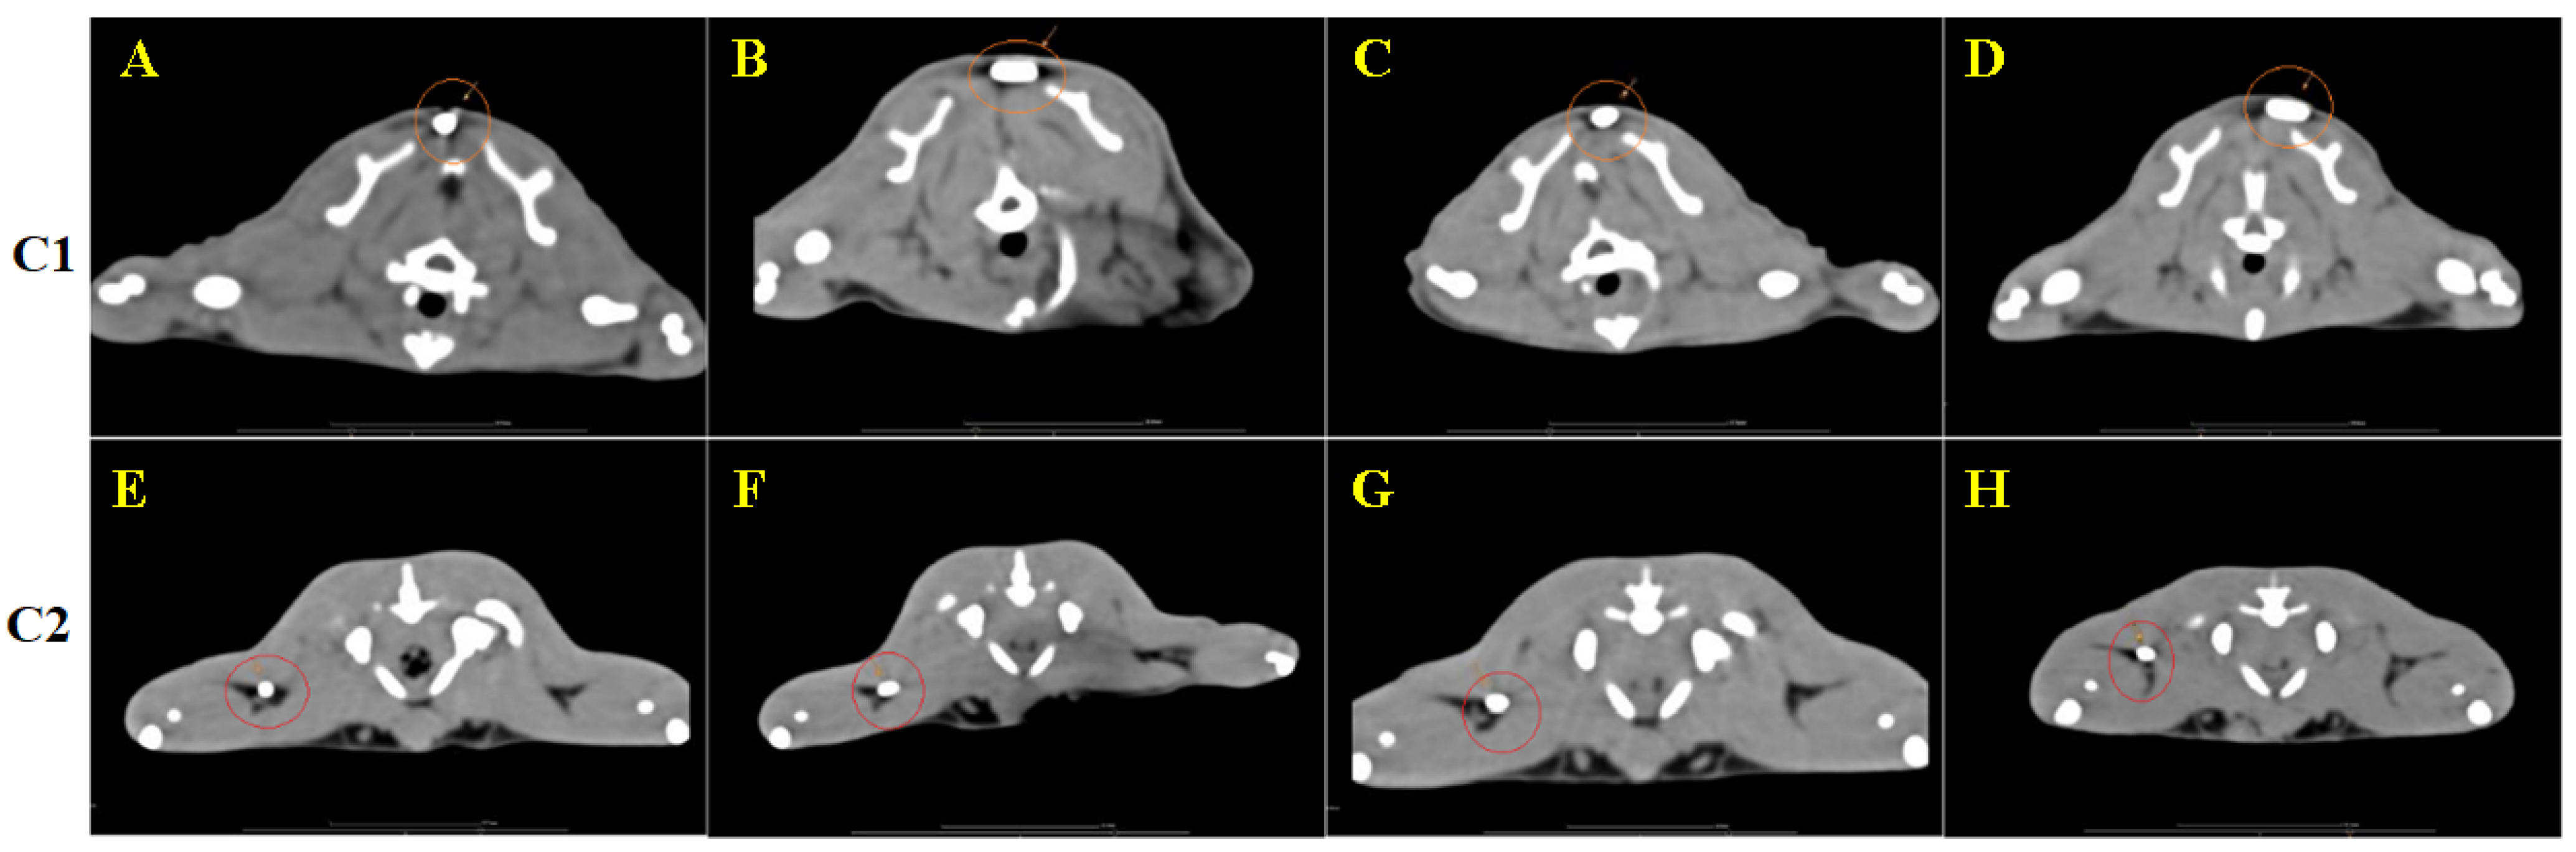

3.4. CT Image Findings